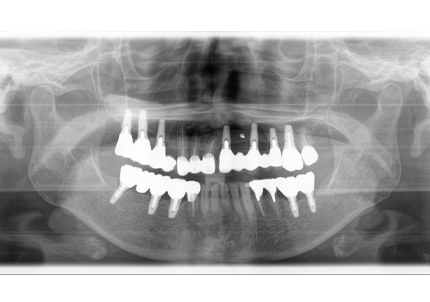

4.左上下7番インプラント補綴物装着(2010年5月24日)

5.右上7番インプラント(2013年11月6日)

6.右下6,7番インプラント(2017年9月15日)

7.左上6番インプラント(2021年2月21日)

8.初診より現在に至る

強い歯ぎしり、くいしばりで奥歯の歯牙破折、深い虫歯で保存不可能となり全顎治療となる。

↑ 2025年9月9日

治療後は経過良好